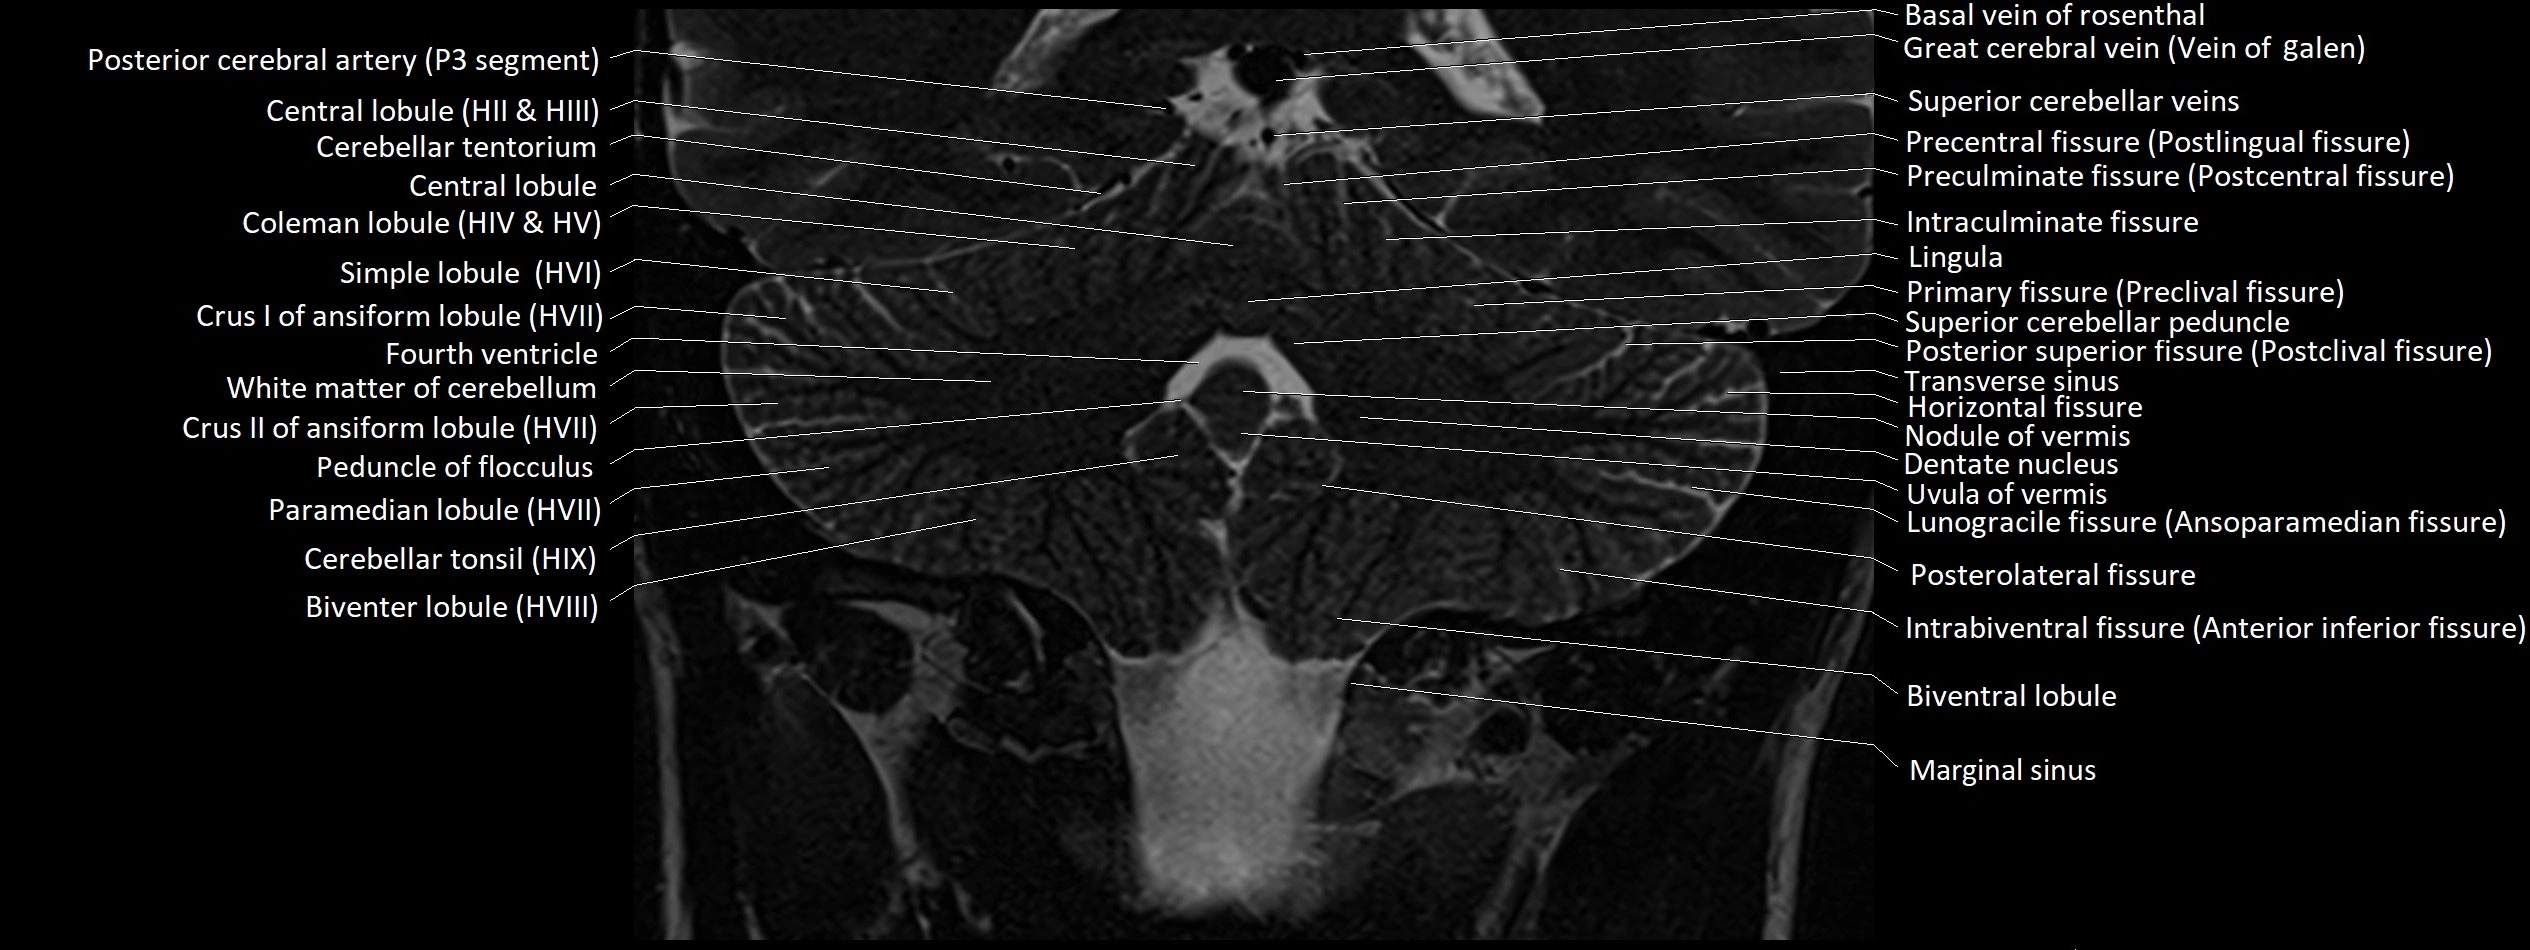

- Anterior lobe of cerebellum

- Biventral lobule (HVIII) of cerebellum

- Central lobule

- Central lobule (II & III) of Cerebellum

- Cerebellar tonsil (H IX)

- Crus I of ansiform lobule of cerebellum

- Crus II of ansiform lobule of cerebellum

- Dentate nucleus

- Horizontal fissure (cerebellum)

- Inferior hemispheric veins of the cerebellum

- Inferior vein of vermis

- Intrabiventral Fissure of Biventral Lobule

- Intraculminate fissure

- Lunogracle fissure

- Marginal sinus

- Middle cerebellar peduncle

- Nodule of vermis

- Occipital sinus

- Paramedian lobule

- Paramedian lobule (HVII) of cerebellum

- Peduncle of flocculus

- Pericallosal cistern

- Posterolateral fissure

- Precentral fissure

- Preculminate fissure

- Primary fissure

- Simple lobule

- Simple lobule (HVI) of cerebellum

- Superior cerebellar peduncle

- Transverse sinus

- Uvula of vermis

- White matter of cerebellum (Arbor vitae)